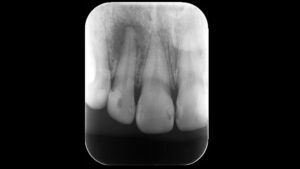

最初は自覚症状が少ないこともありますが、レントゲンを撮ると歯の根の周りに「透過像」と呼ばれる黒い影(骨がなくなっている部分)がはっきりと確認できるようになります。

一般的なレントゲン診断の限界

多くの歯科医院で使用されている2次元のデジタルレントゲンは、非常に優れた装置ですが、情報量に限界があります。

歯の重なりや角度によっては、微細なひび割れ(破折線)が写らないことも珍しくありません。

この場合、歯科医師は臨床経験や周囲の骨の溶け方から「おそらく破折しているだろう」という推測を交えて判断を下すことが一般的です。

これは決して不誠実なことではなく、標準的な設備環境における「安全を考慮した診断」と言えます。